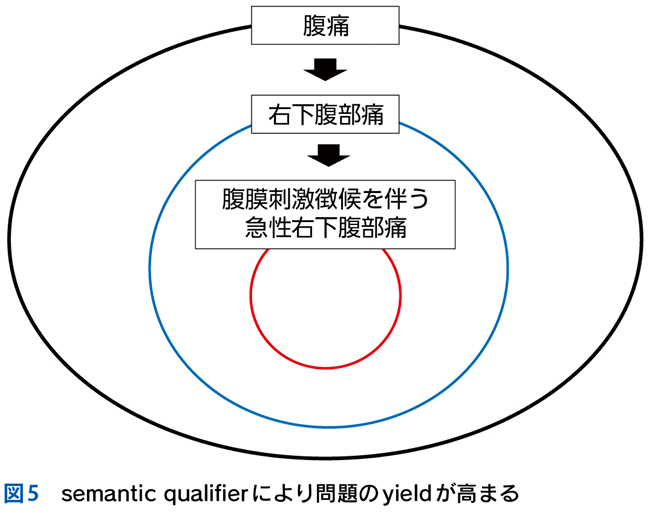

▶ 「yieldの高いプロブレムを同定し問題の中心に据える」以外に問題のyieldを高める方法として,プロブレムを医学的用語で「修飾(qualify)」することがある。「発熱」というプロブレムはlow yield(二等星)だが,修飾を加えて「左下腹痛を伴う急性発熱」や「CRP陰性の遷延性発熱」という問題となればかなりyieldは上がる。このように,中心に据えたプロブレムがlow yieldでも,修飾することでhigh yieldとなり,「適切な問題」となりうる(図5)。この際に利用する医学的修飾語句をsemantic qualifier(SQ)と呼ぶ。